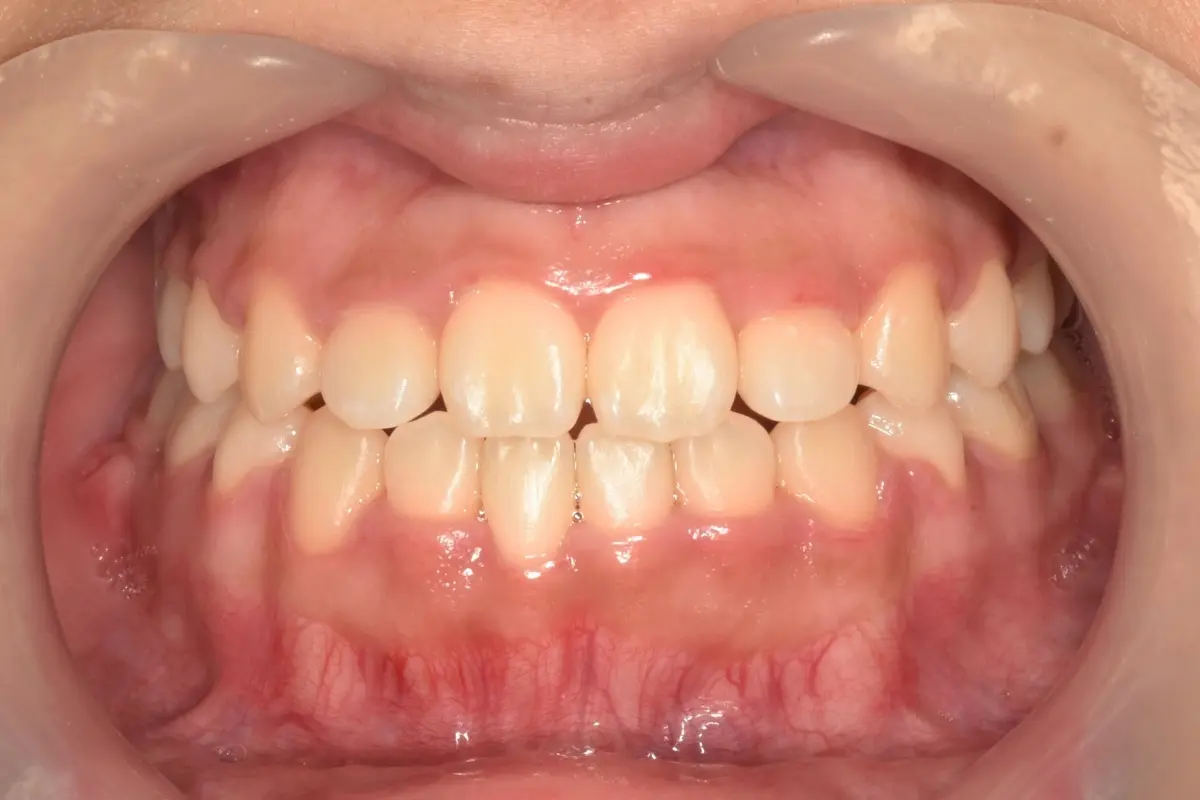

• 術前 44

術後 42

仿生美學樹脂

主治醫師

• 陳暐文

治療時間

單次療程

主訴

門牙有縫、牙齒形狀偏方,笑起來不夠自然